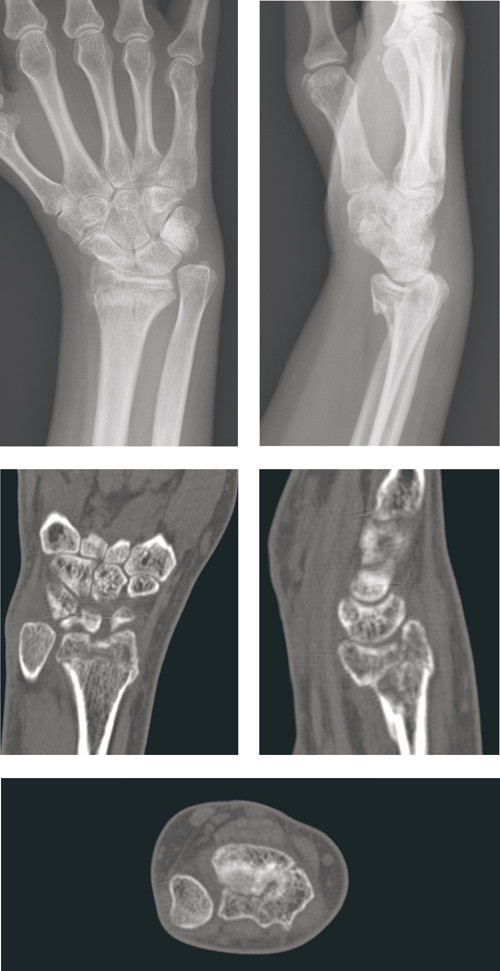

Figure 1  Radiological result after conservative treatment of unstable, intra-articular distal radius fracture in patient in…

Figure 1 Radiological result after conservative treatment of unstable, intra-articular distal radius fracture in patient in the 40s. A 7 mm shortening of the radius is seen and a 2 mm step on the joint surface in both the radiocarpal and distal radio-ulnar joint. Functional result of treatment: no rotation movement, very limited flexion and extension and pain that is a constraint on function.